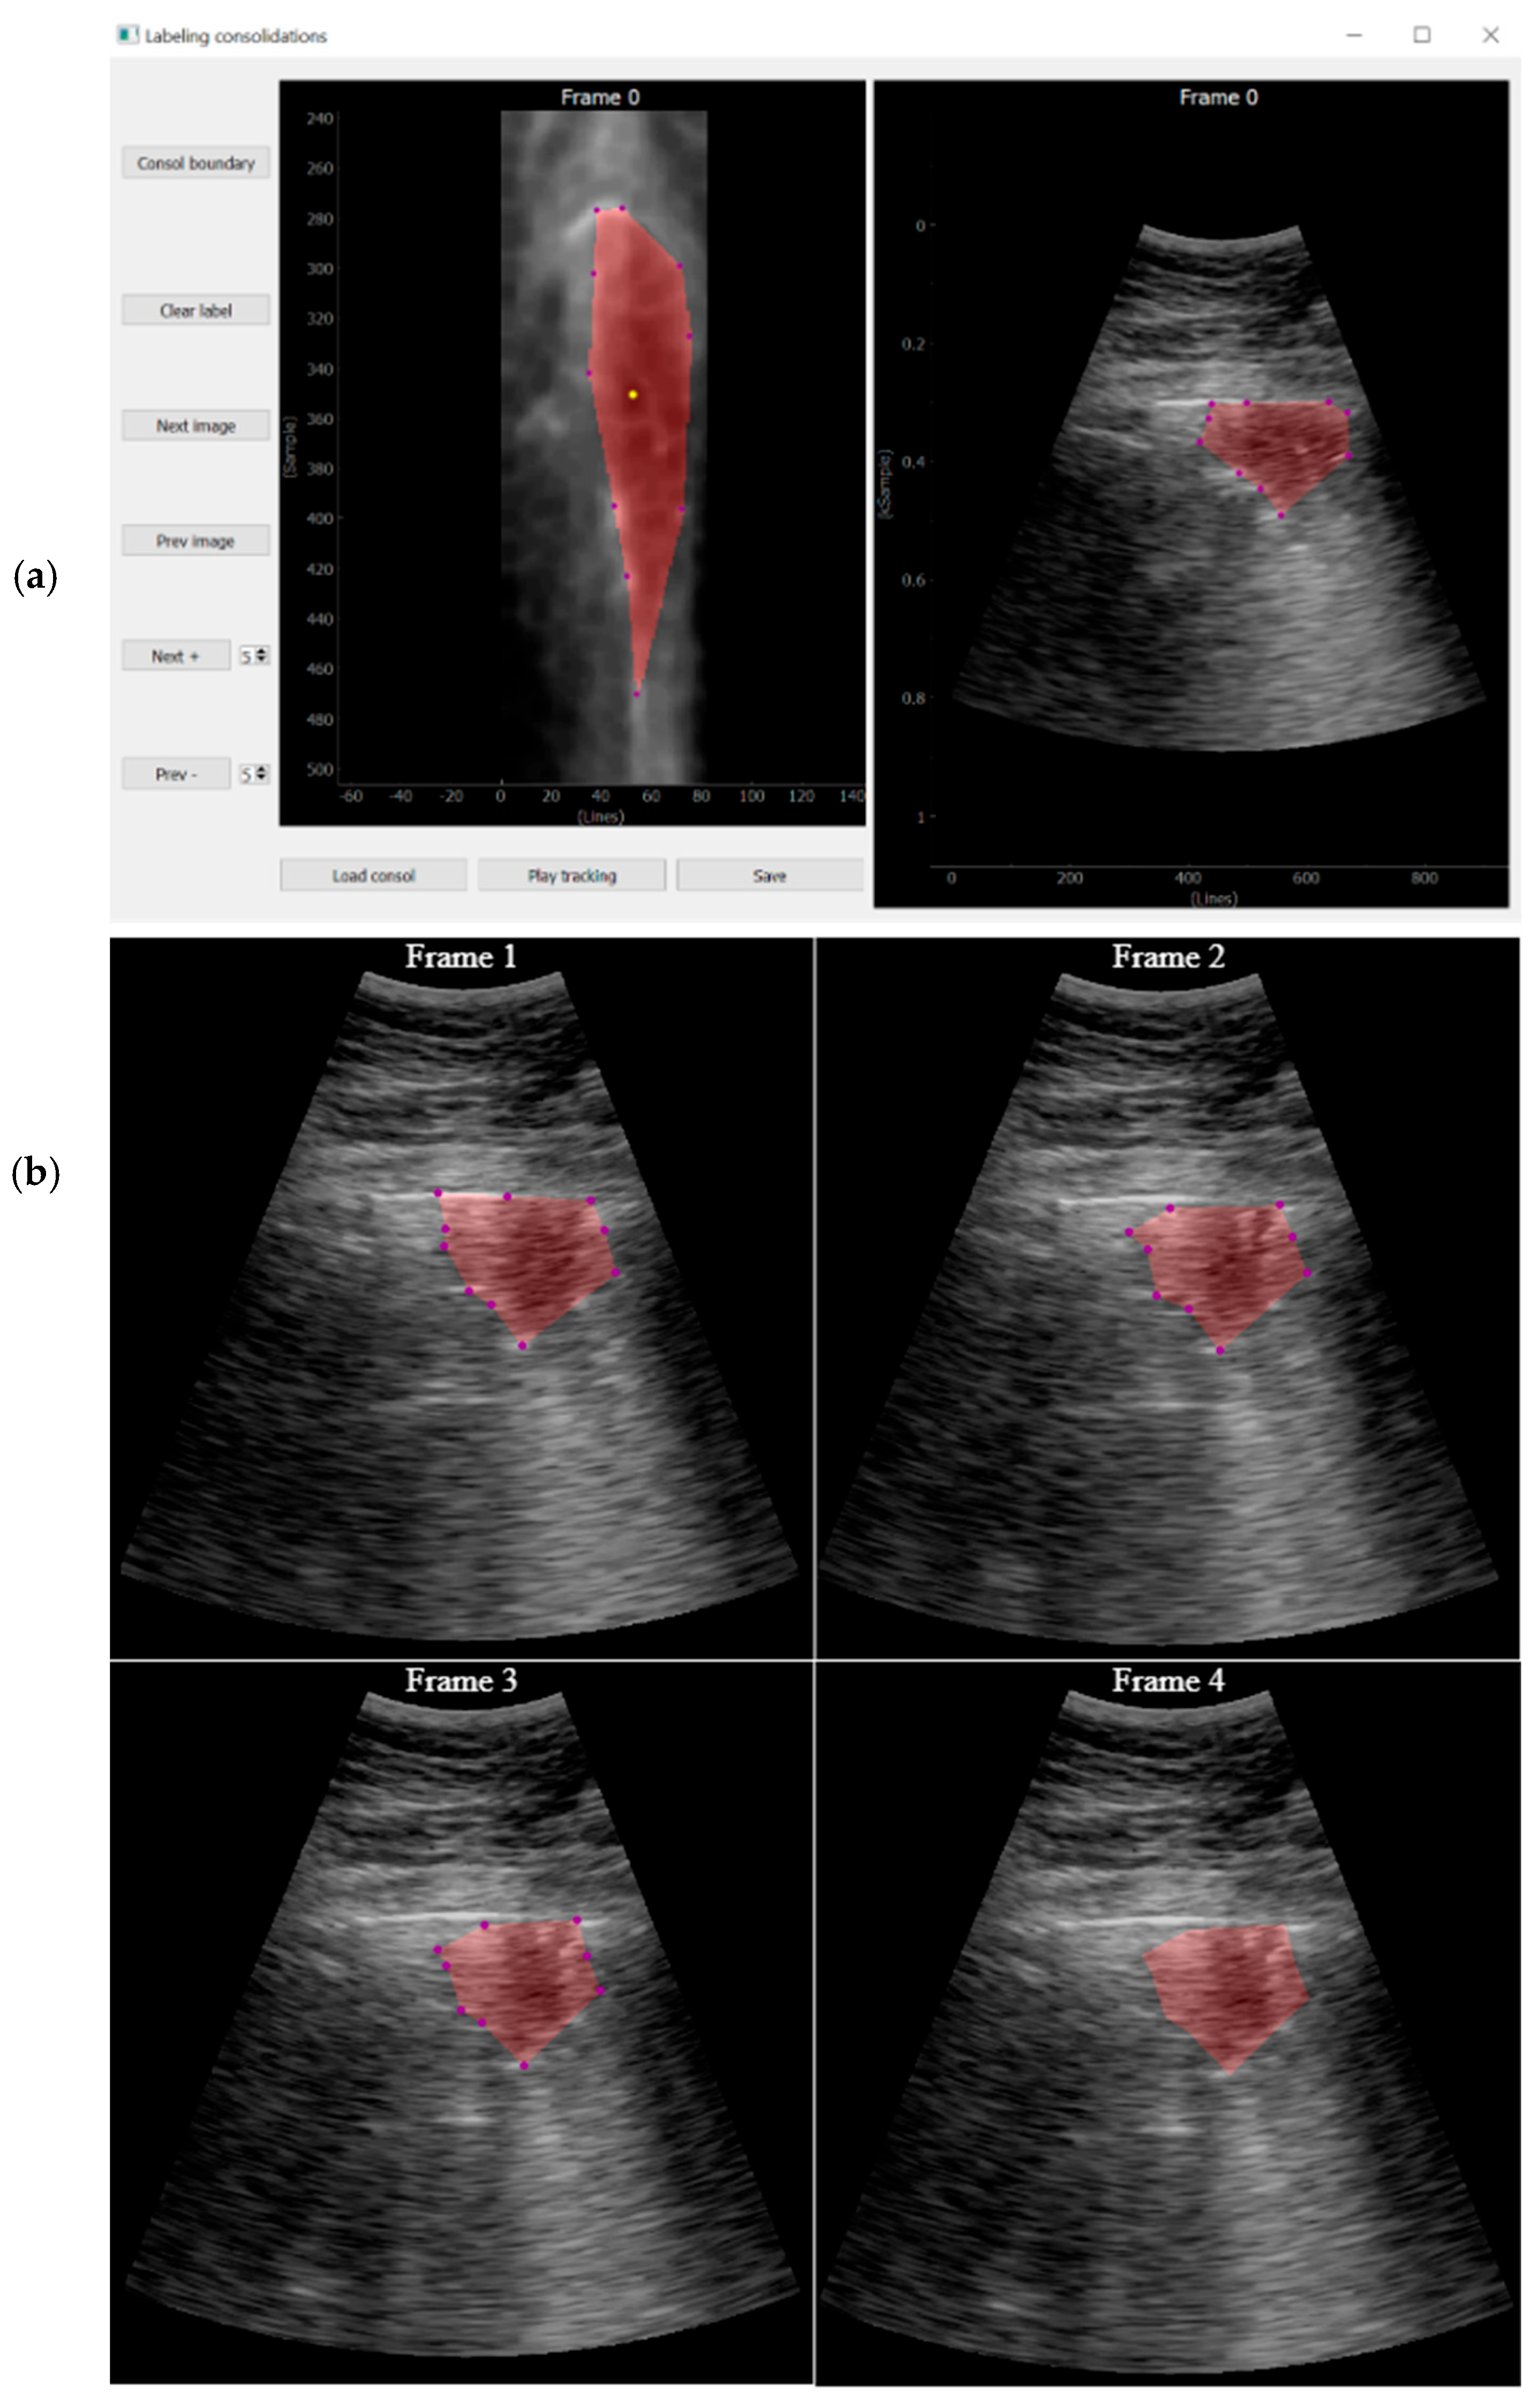

Consolidation Labelling

While pleura, A-lines, and B-lines can be robustly detected by quite simple algorithms applied along each scan line, the consolidations cannot be tackled with the same approach. As they are intrinsically two-dimensional structures, it is not possible to detect them on a line-by-line basis, and image algorithms are needed.

The approach followed in this work was that, given a video labeled by the expert as containing a consolidation, a key frame where this consolidation is seen is first identified. Then, it is manually delineated using a custom developed interactive tool (Figure 9). Finally, an optical flow algorithm [27,28] tracks the movement of the consolidation in the subsequent frames, automatically generating the ground truth masks for the entire video. The optical flow algorithm is based on the principle of selecting a set of reference points and tracking them through the video. This algorithm is particularly suited for ultrasound images because the texture generated by the image speckle can be used for this purpose. The implemented application requests frame-by-frame validation from the user to ensure correct labelling. In case the algorithm fails in the detection, the points of interest will be re-selected again.

Figure 9.

(a) Tool developed for consolidation annotation; (b) tracking secuence over four consecutive frames.